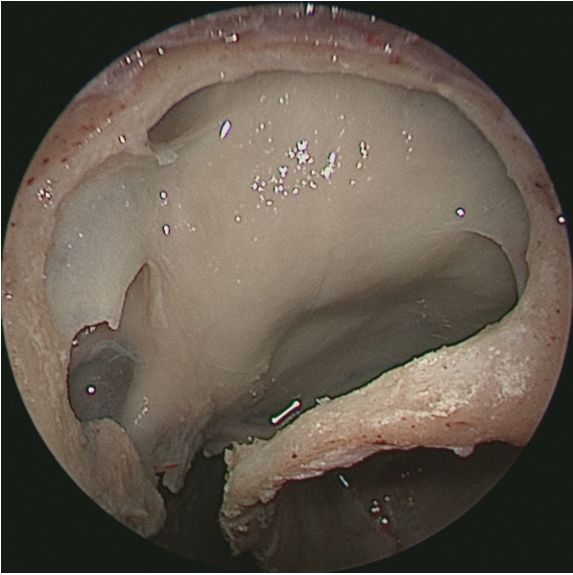

切除中鼻甲后观察鼻腔内整体空间形态